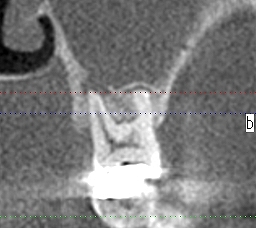

左上6番による歯性上顎同炎。 CT精査。| |広島市安佐南区の歯科医院 左上6番による歯性上顎同炎。 CT精査。 トップ お知らせ・ブログ 左上6番による歯性上顎同炎。 CT精査。 左上6番による歯性上顎同炎。 CT精査。 Web診療予約 初めての方へ 選ばれ続ける理由 院内設備について 歯が痛いしみる一般歯科 歯がぐらぐらする歯周病 健康な歯を保ちたい予防歯科 子供の虫歯予防をしたい小児歯科 銀歯をセラミックに審美歯科 白い歯を目指しませんか?ホワイトニング 矯正専門医がいるので安心矯正歯科 抜けた歯を補いたいインプラント・入れ歯 医院案内 スタッフ紹介 メリィハウス歯科クリニックオフィシャルホームページ ラベンダー歯科クリニックオフィシャルホームページ お知らせ・ブログ ホーム 診療科目 一般歯科 歯周病治療 予防治療 小児歯科 審美治療 ホワイトニング 矯正歯科 入れ歯・インプラント マウスピース矯正 初めての方へ 院長・スタッフ 設備紹介 医院案内・アクセス メニューを閉じる